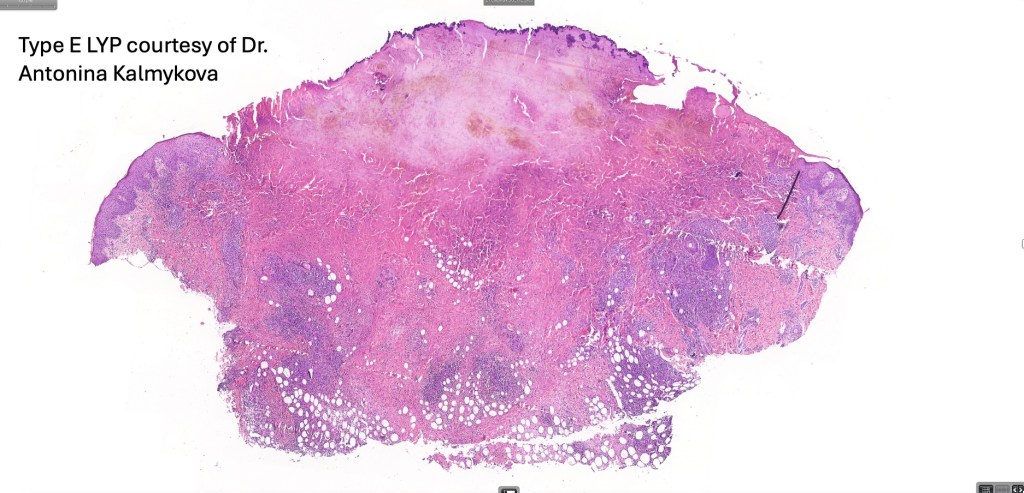

•Type E: angioinvasive & angiodestructive

•Variable epidermal necrosis, epidermotropism, edema, hemorrhage & vasculitis/thrombosis